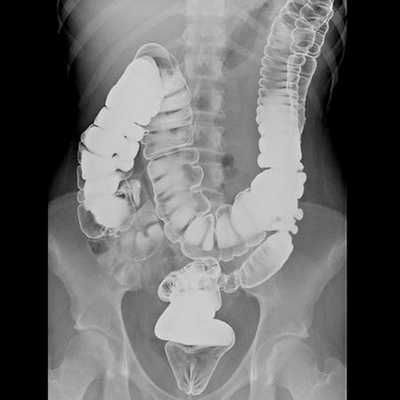

Ирригоскопия с двойным контрастированием. Вы получаете клизму с веществом под названием «барий», а после нее — воздушную клизму. Внутри толстой кишки образуется контур, что позволяет врачу рассмотреть границу толстой кишки в рентгеновских лучах.